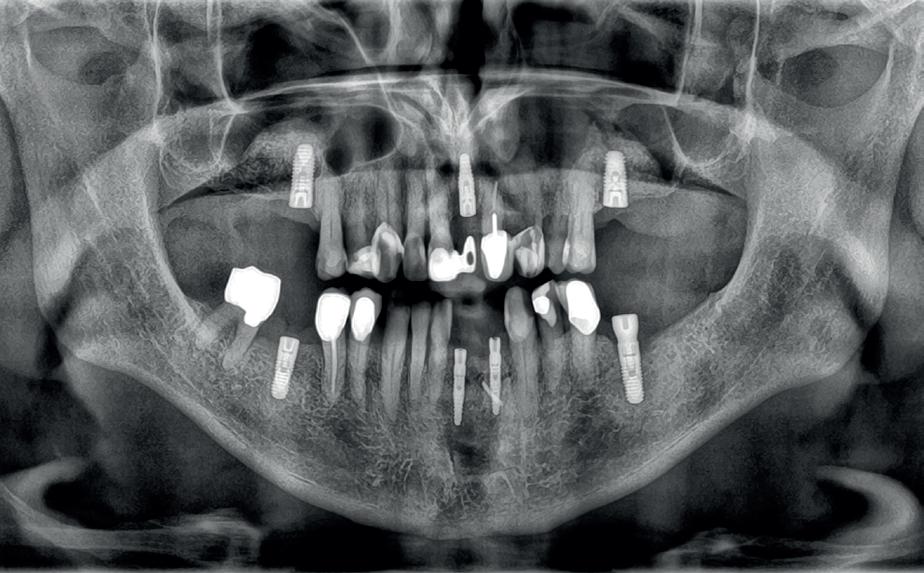

Uitvoering restauratieve fase

In het onderfront werd autoloog bot geoogst uit de kin regio ten behoeve van augmentatie (afbeelding

9. Botopbouw onderfront

10. OPT-implantaten

9). In de bovenkaak werd bilateraal een sinuslift uitgevoerd. Aansluitend werden in beide kaakhelften implantaten geplaatst (afbeelding 10).